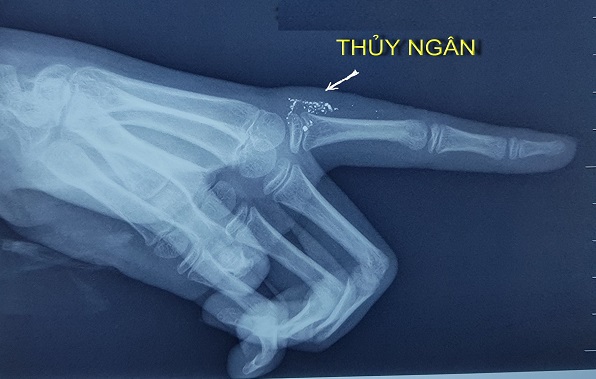

Bé gái 11 tuổi nhiễm độc thủy ngân do vỡ nhiệt kế

Chiều 27-2, theo tin từ Bệnh viện Bạch Mai, khoa Nhi và Trung tâm Chống độc của bệnh viện đang điều trị cho bé gái N.N.Y (11 tuổi, ở tỉnh Thái Bình) bị nhiễm độc thủy ngân qua da do tai nạn hy hữu khi người nhà vẩy nhiệt kế thủy ngân.